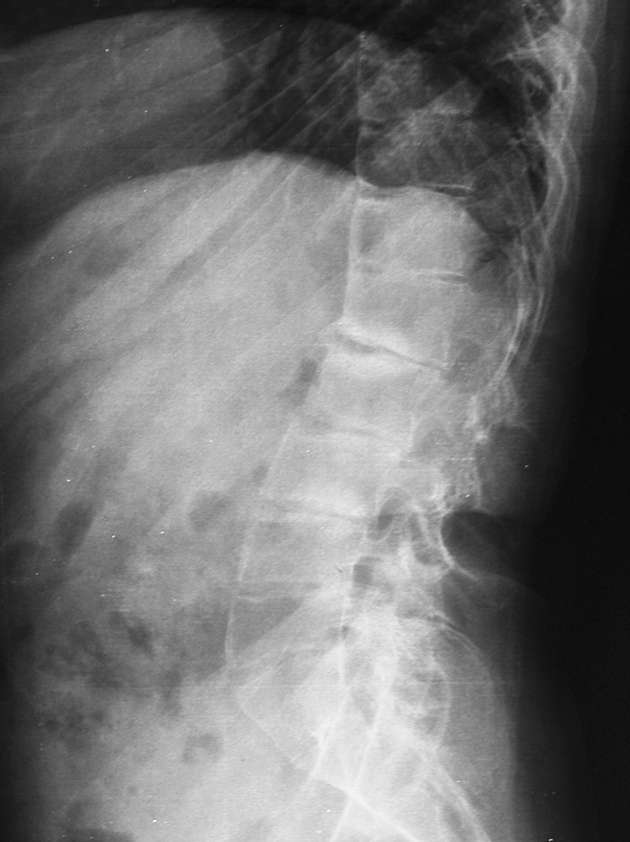

女性34岁,左髋疼痛5年,伴有背部疼痛,腰部活动受限,局部有压痛。

腰椎、左侧骶髂关节及双侧髋关节间隙变窄,左侧明显且有软骨下局部骨硬化,首先考虑强制性脊柱炎,鉴别包括类风湿性关节炎、沙门氏菌骨关节感染及布氏菌骨关节感染等。

腰椎、左侧骶髂关节及双侧髋关节间隙变窄,左侧明显且有软骨下局部骨硬化,首先考虑强制性脊柱炎.

腰椎竹节样改变,考虑强直性脊柱炎